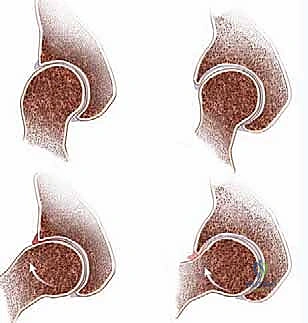

1. Cam FAI is caused by deformities of the femoral head (eg, pistol grip deformity, aspheric femoral head, slipped capital femoral epiphysis).

1. The aspherical head–neck junction is jammed into the acetabulum, leading to a labrocartilaginous separation and shearing of the acetabular cartilage from the subchondral bone (

FIG 1A

).

2. Cartilage damage can be extensive, with flaps or defects involving as much as 15 mm toward the center of the joint.

2. Pincer FAI is caused by local (eg, acetabular retroversion) or general (eg, coxa profunda, protrusio) acetabular overcoverage in the presence of a normal proximal femur, leading to a linear contact between the acetabular rim and

femoral neck that results in degenerative tears and ossification of the labrum.

3. Only a narrow strip of acetabular cartilage is involved along the acetabular rim (

FIG 1B

1. Isolated cam or pincer FAI is rare. In most cases, a combination of both types is present.

1A 1B

FIG 1•

Schematic depictions of cam (

A

) and pincer (

B

) impingement.

A.

In cam impingement, the aspheric anterolateral head–neck junction is forced into the acetabulum, creating shear and stress injury to the acetabular cartilage along the anterosuperior rim.

B.

In pincer impingement, the head–neck junction is normal, but the acetabulum is deep. The labrum is squeezed between femoral neck and acetabular bone and eventually degenerates and ossifies. The femoral head is levered out posteroinferiorly, leading to a “contrecoup” lesion on the femoral head and acetabulum.